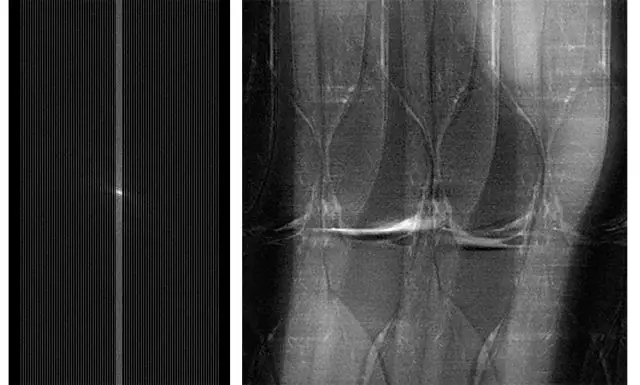

(L)未充分采样的原始 MRI 数据。用于捕获这些数据的 MRI 扫描比用于捕获诊断研究的完整数据的扫描更快,但是未充分采样会在结果的 MRI 图像中产生噪声和伪影。(R)从子样本数据重建的膝盖 MRI 图像。fastMRI 项目旨在使用 AI 创建有用的 MRI 图像,没有像这里显示的噪声和伪影。